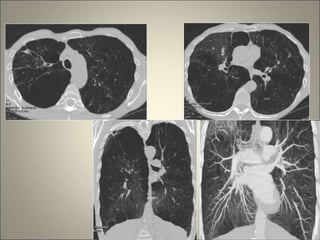

• Déficit en α1 anti trypsine : EPL avec bronchectasies

(40%)

Déficit en α1 AT

Aspects TDM deDBP zones d’hypodensité avec ou sans

piégeage expiratoire , emphysème , épaississement des

parois bronchiques , opacités linéaires et triangulaires

sous pleurales , images en mosaïque , prédominance lobes

inférieurs